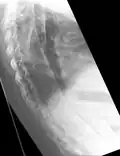

X-rays

The earliest changes demonstrable by plain X-ray shows erosions and sclerosis in sacroiliac joints. Progression of the erosions leads to widening of the joint space and bony sclerosis. X-ray spine can reveal squaring of vertebrae with bony spur formation called syndesmophyte. This causes the bamboo spine appearance. A drawback of X-ray diagnosis is the signs and symptoms of AS have usually been established as long as 7–10 years prior to X-ray-evident changes occurring on a plain film X-ray, which means a delay of as long as 10 years before adequate therapies can be introduced.[25]

Options for earlier diagnosis are tomography and MRI of the sacroiliac joints, but the reliability of these tests is still unclear.

Lateral X-ray of the mid back in ankylosing spondylitis -

X-ray showing bamboo spine in a person with ankylosing spondylitis -